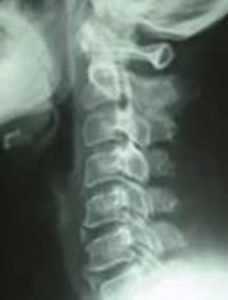

中央部の縦に白い線が骨化巣です。

後縦靱帯骨化症になると、脊髄の前方にある「後縦靱帯」が肥厚して、骨化します。すると、脊髄が走っている脊柱管が狭くなって、脊髄や脊髄から枝分かれした神経根が圧迫されて、知覚や運動などの神経障害が起こります。この症状は、病気であり、交通事故によって後縦靱帯が骨化することはありません。

この場合、実際に後縦靱帯骨化症となっていて、レントゲンやCTで骨化巣(骨化した部分)が確認できたときには、疾患とされることを避けられません。素因減額は免れませんし、後遺障害認定も受けにくくなります。